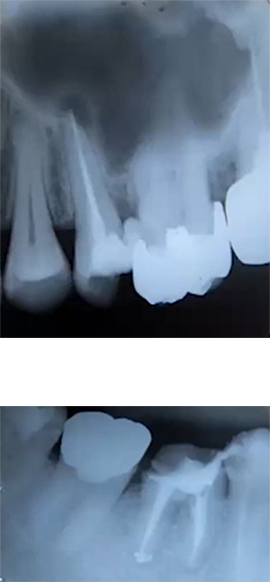

| 日常臨床で行われている抜髄や感染根管治療は、基本に則り忠実に治療を行えば多くの症例は治癒に向かうことが多い。しかしながら、根管充填処置を行ったものの咀嚼時痛や打診痛などの症状がなかなか消失せず、いわゆる難治性根尖性歯周炎と診断され、再根管治療を余儀なくされる症例も少なからず存在する。今回のセミナーでは、そのような対応に苦慮する再根管治療を必要とする症例の原因とその対処法などについて、実際の症例を提示しつつ考察したいと思う。 |

≪レクチャー≫ ◆再根管治療となる原因 ◆再根管治療歯に潜む問題点 ◆各種偶発症への対処法 ◆根管治療の精度を高めるには? ◆再根管治療を防ぐために

日常臨床で行われている抜髄や感染根管治療は、基本に則り忠実に治療を行えば多くの症例は治癒に向かうことが多い。しかしながら、根管充填処置を行ったものの咀嚼時痛や打診痛などの症状がなかなか消失せず、いわゆる難治性根尖性歯周炎と診断され、再根管治療を余儀なくされる症例も少なからず存在する。今回のセミナーでは、そのような対応に苦慮する再根管治療を必要とする症例の原因とその対処法などについて、実際の症例を提示しつつ考察したいと思う。 ご略歴 ●1983年 東京歯科大学卒業 ●2013年~ 東京歯科大学歯内療法学講座 教授